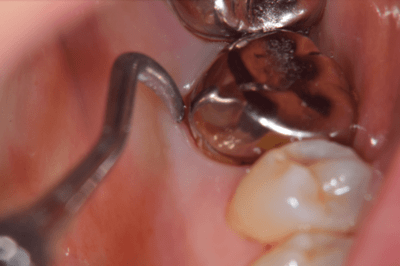

歯が大きく欠けた

歯ぐきが治癒した

説明:

右上の歯が大きく欠けています。黒く虫歯になっているのがわかります。移植を計画しましたので、歯ぐきがしっかり治癒するのを(1ヶ月)待ちました。